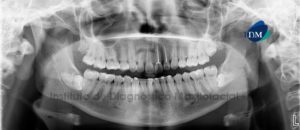

Paciente femenino de 55 años de edad que es referida por presentar dolor en la pieza 26. La radiografía panorámica nos muestra un trazo de